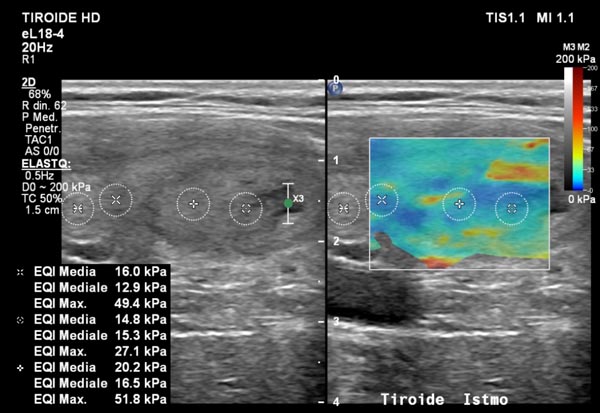

Elastosonografia tiroidea: diagnosi più precisa dei noduli?

Un altro campo in cui l’elastosonografia ha cambiato la pratica clinica è lo studio dei noduli tiroidei.«I noduli più rigidi possono essere sospetti e meritano approfondimento, mentre quelli più morbidi sono generalmente benigni. Grazie a questa metodica possiamo selezionare i casi che necessitano di un agoaspirato (FNAB) e monitorare nel tempo eventuali cambiamenti».In questo modo l’elastosonografia tiroidea diventa uno strumento prezioso per ridurre biopsie inutili e migliorare l’accuratezza diagnostica.

Un supporto prezioso alla diagnosi quindi, non un suo sostituto.

L’elastosonografia non sostituisce la diagnosi istologica, ma la integra con un’informazione aggiuntiva e non invasiva.«Il valore reale — sottolinea Ivona — è nel contesto clinico: il risultato va interpretato alla luce della storia del paziente, degli esami di laboratorio e delle immagini ecografiche tradizionali».Il vantaggio è evidente: migliorare la precisione diagnostica, ridurre i rischi e rendere il percorso di cura più personalizzato.